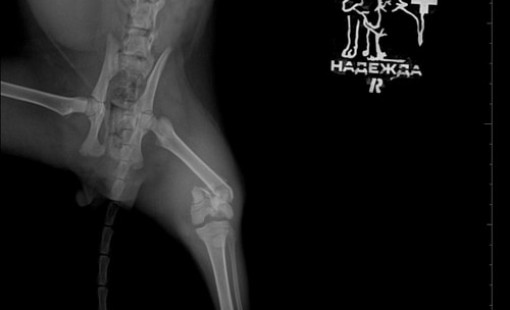

Случаи из практики

Ветеринарная клиника Надежда

За более чем 30-ти летнюю практику наши ветеринары сталкивались в различными случаями болезней и травм животных. Это дало нам огромный опыт в лечении и реабилитации. Мы беремся даже за самые сложные случаи! С любовью и заботой относимся к животным, стараемся сделать так, чтобы они испытывали минимум дискомфорта во время лечения и реабилитации.